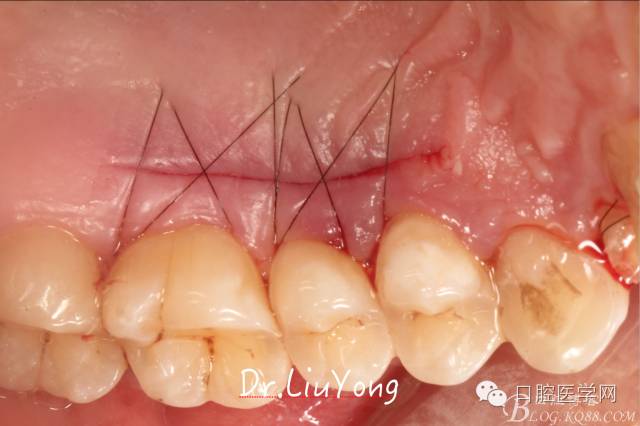

將結(jié)締組織瓣縫合固定于受區(qū),如上圖